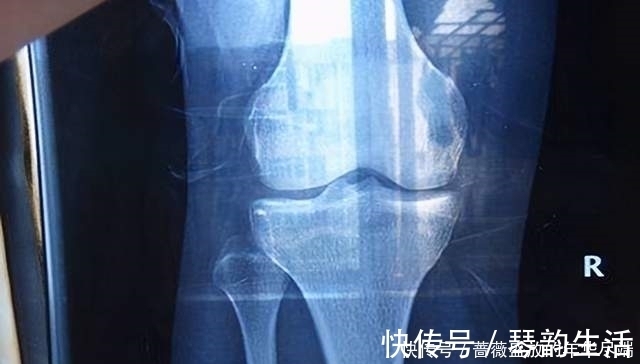

因为人的骨骼发育需要钙,而性早熟的孩子钙储备并不多,并且性早熟会加速骨骼骨骺线闭合,所以孩子会暂停长个。